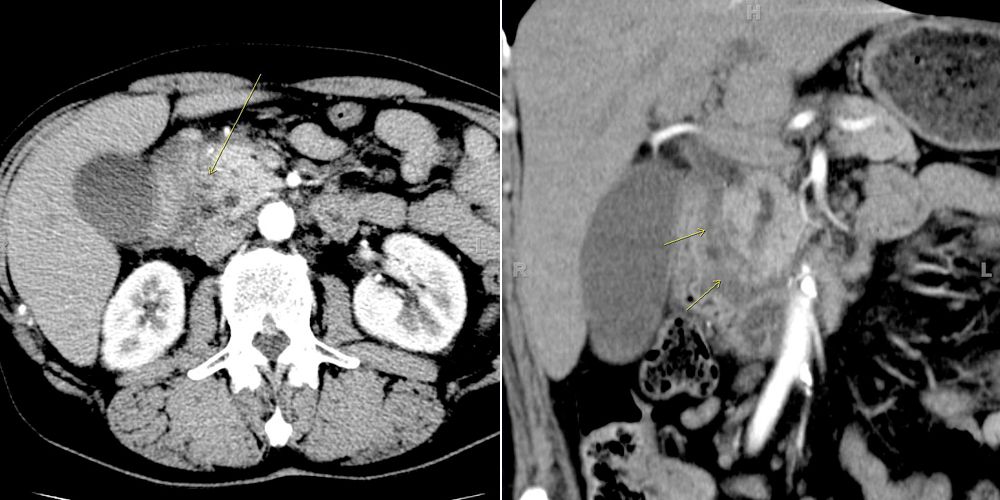

A 52-year-old man with a history of heavy alcohol use and chronic abdominal pain presents with the following CT scan. What is your diagnosis?

A 52-year-old man with a history of heavy alcohol use and chronic abdominal pain presents with the following CT scan.

What is your diagnosis?